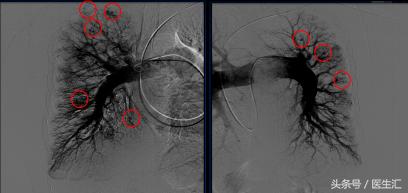

肺动脉造影+右心导管检查

造影所见:肺动脉主干及叶肺动脉明显增粗,双侧肺动脉分支未见明显扭曲,未见明显充盈缺损,可见弥漫性动静脉瘘,远端灌注良好

【右心导管检查】毛细血管前肺动脉高压,急性肺血管扩张试验阴性